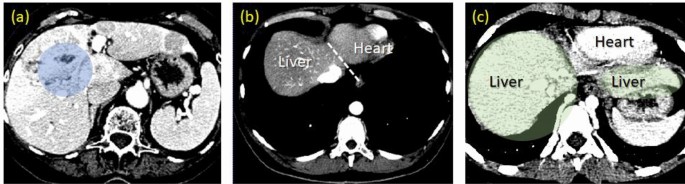

Liver is the largest organ in the abdomen. It functions as a filter, which prevents waste and other toxins being released into the circular system. Because a diseased liver cannot properly maintain its performance, earliest detection of pathological manifestations ensures the effectiveness of treatments, and hence prolonging patient’s life. Moreover, modern developments in therapeutic intervention and surgery have increasingly relied on computerized reconstruction of a subject-specific liver, both for treatment planning and in subsequent proceeding. Computed Tomography (CT) is one of the primary modalities preferred in those platforms. It allows the physician to clearly visualize anatomical structure of this organ as well as pathological evidence. However, prognostic assessment during a treatment requires standardized protocols, which in turn call for quantitating pathological indicators. They usually involve delineation of liver, its peripherals, and lesions (if any) by an experienced and skilled radiologist. The process is known for being laborious, time consuming, and prone to inter- and intra-observer variabilities. Recently, it has been even more so, given increasing resolution of a 3D matrix acquired by a modern CT1,2,3,4. Consequently, fully- and semi-automatic system has become vital in Computer Aided Diagnosis (CAD). Unlike other imaging protocols, however, CT liver is difficult to be segmented, due to inheriting challenges (Fig. 1).

Challenges associated with liver segmentation, i.e., inhomogeneity of intensity in the liver region (a), fuzzy separation between liver and heart (b) and the multi-segments geometry within single slide (c). In addition, these cases exhibit different intensity ranges of liver tissue.

Since CT element represents tissue as its X-ray absorption, it does inevitably not differentiate well adjacent organs with similar properties, such as kidney, heart, and muscle from the liver. In addition, there is no edge gradient sufficiently strong to be identified as a boundary separating these objects. In fact, inhomogeneity of liver interior is much pronounced than that against non-liver regions, leading to low segmenting accuracy. Disease induced changes and deformity1,5,6, motion artefacts, as well as inter-subject variability, also worsen the outcomes. Last but not least, as the liver geometry is very complex but still singly connected, it may appear as separate regions in some slices. Simplifying 3D segmentation to 2D contour tracing is not trivial. Due to these challenges, faithfully segmenting a liver from volumetric CT images thus largely remains an open area of investigation.